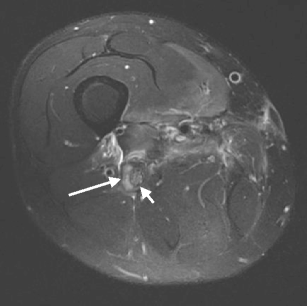

Sneag DB, Saltzman EB, Meister DW, Feinberg JH, Lee SK, Wolfe SW (2016) MRI bullseye sign: An indicator of peripheral nerve constriction in parsonage-turner syndrome. Muscle Nerve. doi:10.1002/mus.25480